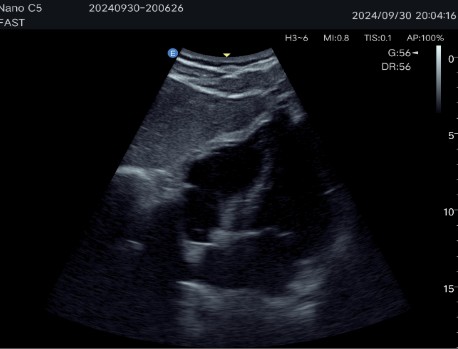

Auto B-Line and Fast/eFast: Fast navigation protocol for lung condition assessment and emergency diagnosis.

Abdominal diagnostics, obstetrics and gynecology: Allows detailed evaluation of internal organs and structures.